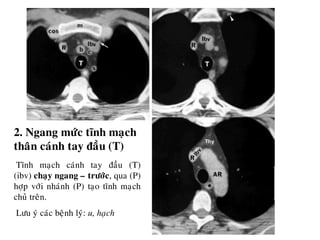

2. Ngang möùc tónh maïch

thaân caùnh tay ñaàu (T)

Tónh maïch caùnh tay ñaàu (T)

(ibv) chaïy ngang – tröôùc, qua (P)

hôïp vôùi nhaùnh (P) taïo tónh maïch

chuû treân.

Löu yù caùc beänh lyù: u, haïch